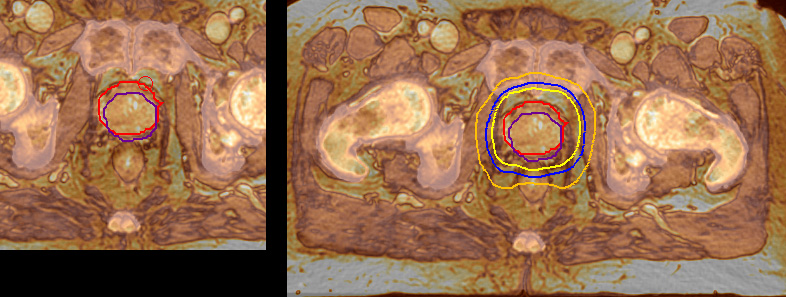

Impressive clinical benefits for prostate

“The biggest problem for CT-based planning, especially in prostate, is you can’t see the cancer very well,” says Dr. Stevens. “On CT it can be quite challenging to see the edge of the prostate especially at the apex. When the edge of the prostate can’t be delineated well on CT, radiation oncologists will increase their margins a little bit so they don’t miss it, but that can also increase toxicity.”

“Using MR, the prostate is well delineated. We quickly see the edges of cancerous tumors like in prostate cancer, and as normal structures can be defined, we can optimize the treatment plan to protect these organs and their normal function. This can potentially improve the outcome. And it improves workflow as well. We can contour more quickly, confident that the tumor is going to be in the field.”

“When a patient registers, first CT simulation and MR simulation are done, followed by CT-MR registration on Pinnacle3. Then the target and normal organ delineation is performed on MR images. Meanwhile we create a reference CT image for online treatment and localization correction. During the treatment phase we can perform additional MRI scans to visualize the anatomy changes and create an adaptive plan. This plan basically adapts the treatment plan to the changes.”